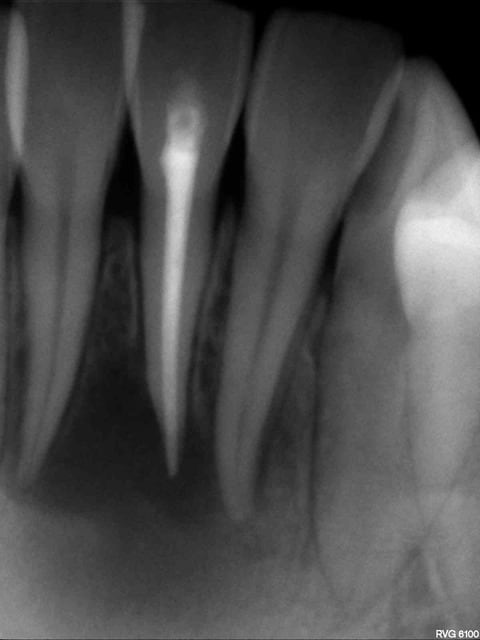

a 3 mois post endo

En comparaison avec les radios initiales, je ne vois pas de changement, ni plus ni moins. Surveillance à 6 mois ? De toute façon, l'endo était inévitable, reste à voir si elle se suffit !

voici le contrôle radio a 2 mois: y'a de l'espoir!!!